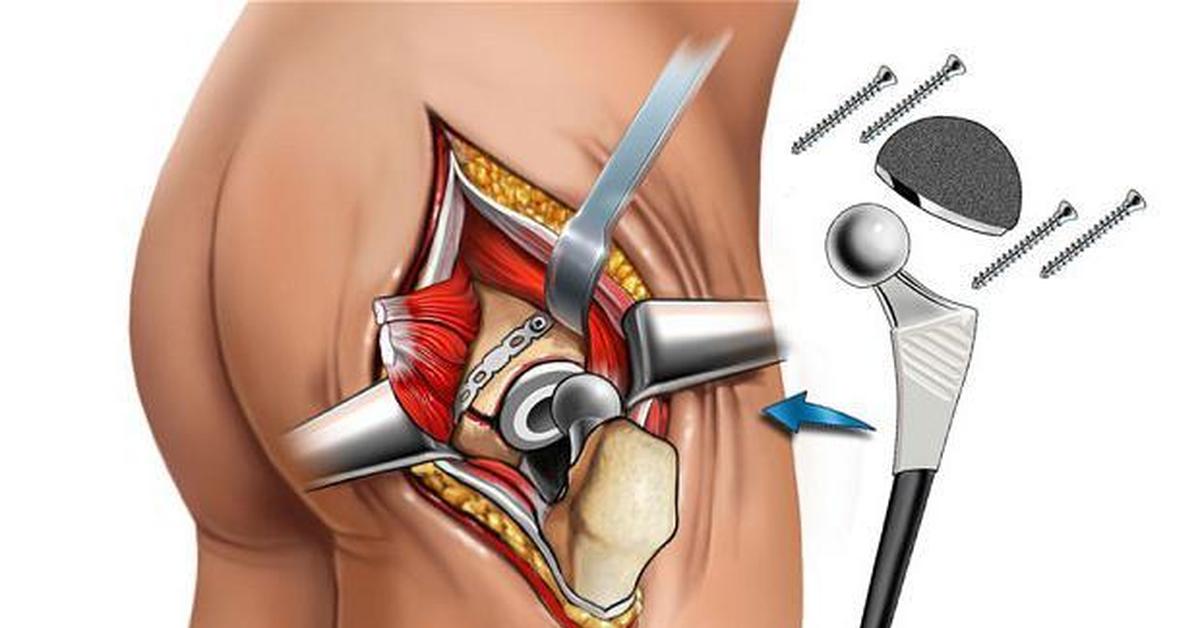

Иллюстрации и снимки, связанные с остеопенией шейки бедра

Раздел: Необычные решения